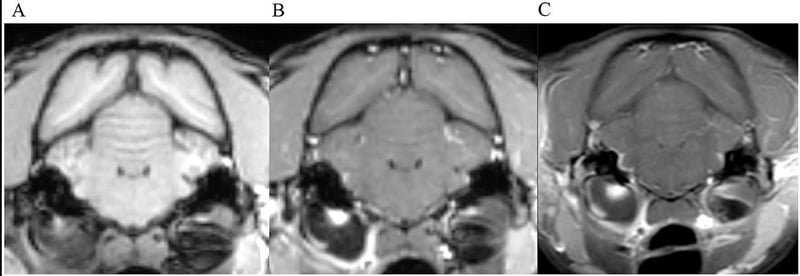

UltrasoundUltrasound